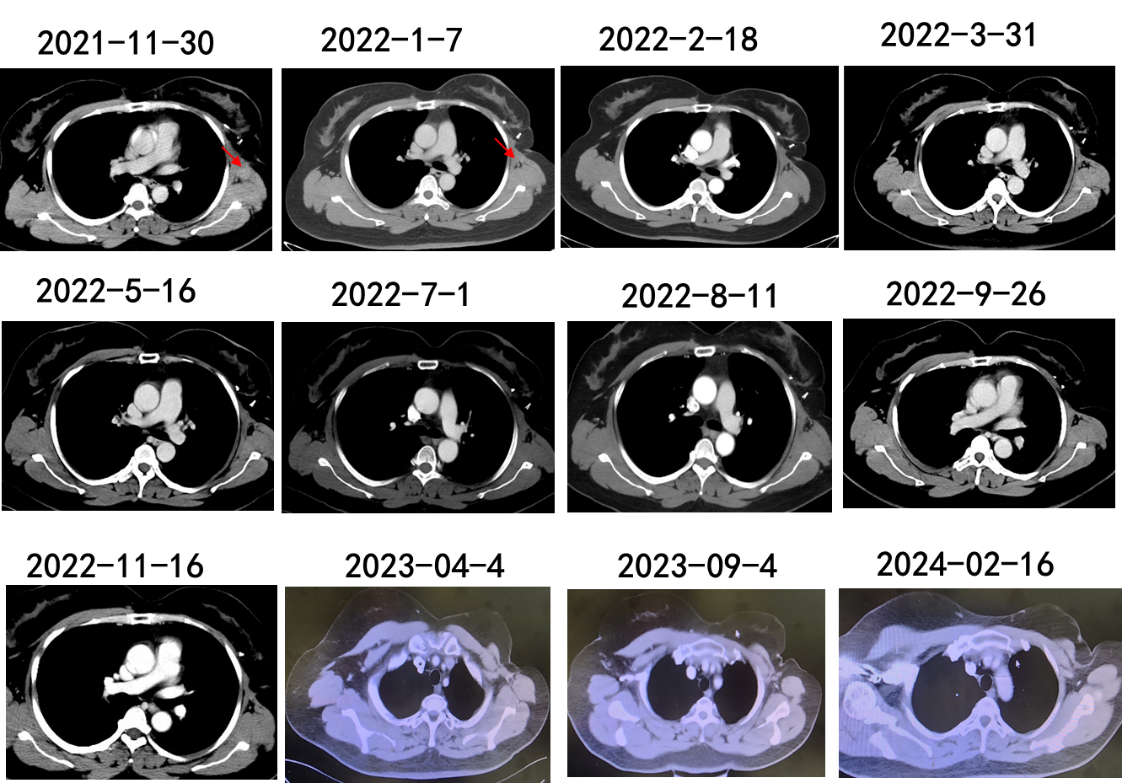

入组“PD-1单抗加安罗替尼联合节拍化疗在晚期三阴性乳腺癌中的疗效、安全性及探索性转化研究”。2021年12月1日至2023年11月24日予长春瑞滨软胶囊40mg po tiw + 安罗替尼12mg d1-14 q21d + 信迪利单抗200mg ivdrip q21d治疗;2023年11月24日起停用信迪利单抗,改为长春瑞滨软胶囊40mg po tiw + 安罗替尼12mg d1-14 q21d维持治疗至今。

疗效与安全性评价:

治疗2周期后达部分缓解(PR),4周期后达CR,后续每2周期复查持续维持CR。治疗期间出现Ⅲ级肝功能异常、Ⅱ级甲状腺功能减低,经对症处理后好转,未影响治疗进程。